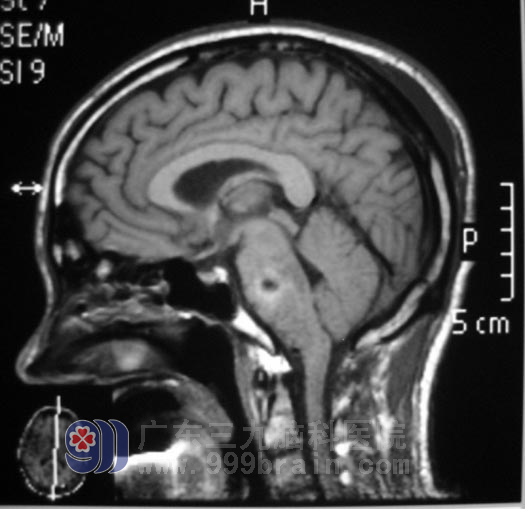

在组织放射科、麻醉科等相关学科协同会诊,确立手术方案后,1月5日由鲁明主任主刀,术中见肿瘤明显压迫舌咽神经、迷走神经、副神经及设下神经,小脑后下动脉、椎动脉与肿瘤紧密联系,肿瘤与脑干粘连紧密,手术难度比预想的大多了,显微镜下将肿瘤顺利切除,整个手术持续近6个小时。手术后的黄先生康复很快。

脑干处手术难度大,手术致残及死亡率较高,预后不良,此处的成功手术一直被认为是神经外科技术水平已进入国内领先行列的标志。

▲手术后